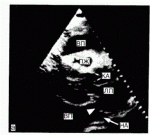

Эхокардиография: Диагностика перикардиального выпота

Эхокардиография - наиболее эффективный и доступный метод диагностики, обладающий достаточной чувствительностью и специфичностью, простой в выполнении, неинвазивный, безвредный; может быть выполнен у постели больного. При наличии небольшого выпота в перикарде выявляется относительно свободное от эхо-сигнала пространство между задней частью перикарда и задней частью эпикарда левого желудочка. При